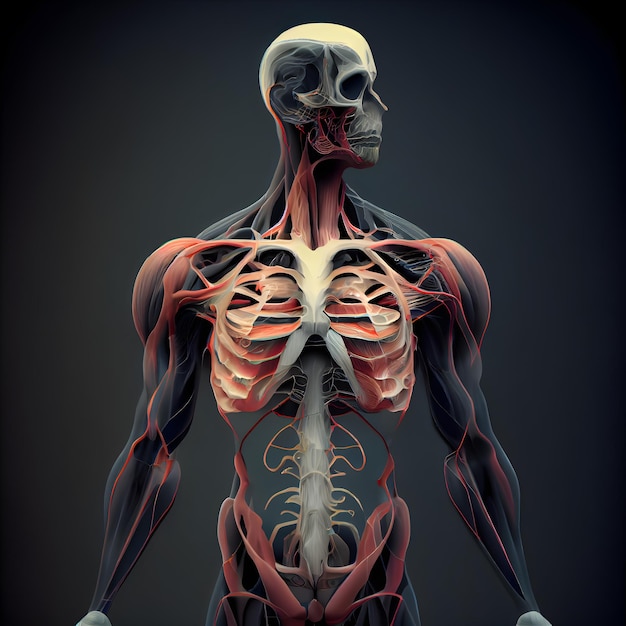

Анатомия человека: кровеносная система и её связь со скелетом